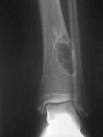

El diagnostico del fibroma desmoplástico es difícil de hacer radiológicamente. Radiografías simples demuestran lesiones expansibles medulares, de naturaleza osteolítica y márgenes escleróticos propiamente definidos. El tumor ovalado se encuentra frecuentemente en la metafísis a lo largo del eje largo del hueso.

Usualmente la corteza es delgada con lesiones intra-trabeculares que confieren una apariencia lobulada descrita como burbujas. Estudios de TAC son útiles para identificar puntos de rompimiento cortical. Estudios de RNM pueden demostrar la separación del tumor intraóseo del hueso. El diferencial radiológico incluye fibroma no-osificante, tumor de células gigantes, QOU, QOA Y displasia fibrosa.